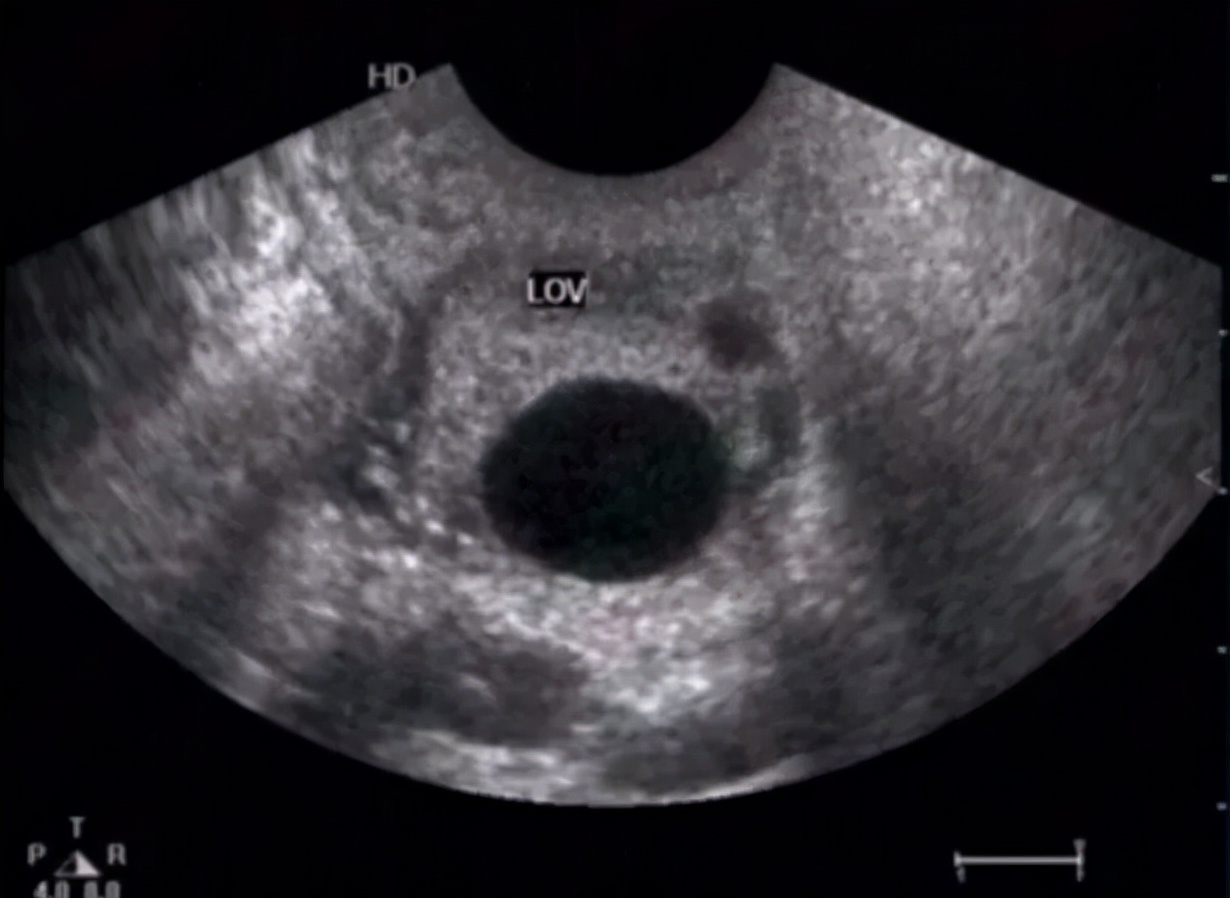

卵巢生理性囊肿特点: 囊壁菲薄,内壁光滑,透声好,直径基本<4-5cm。超声多普勒血流检测提示没有明显的血流信号。多数会消失,一般建议1-3个月后月经干净3天左右复查,因为这时新的一批卵泡尚未发育起来,所有没有二次干扰,可以判断它是否真的消失了。